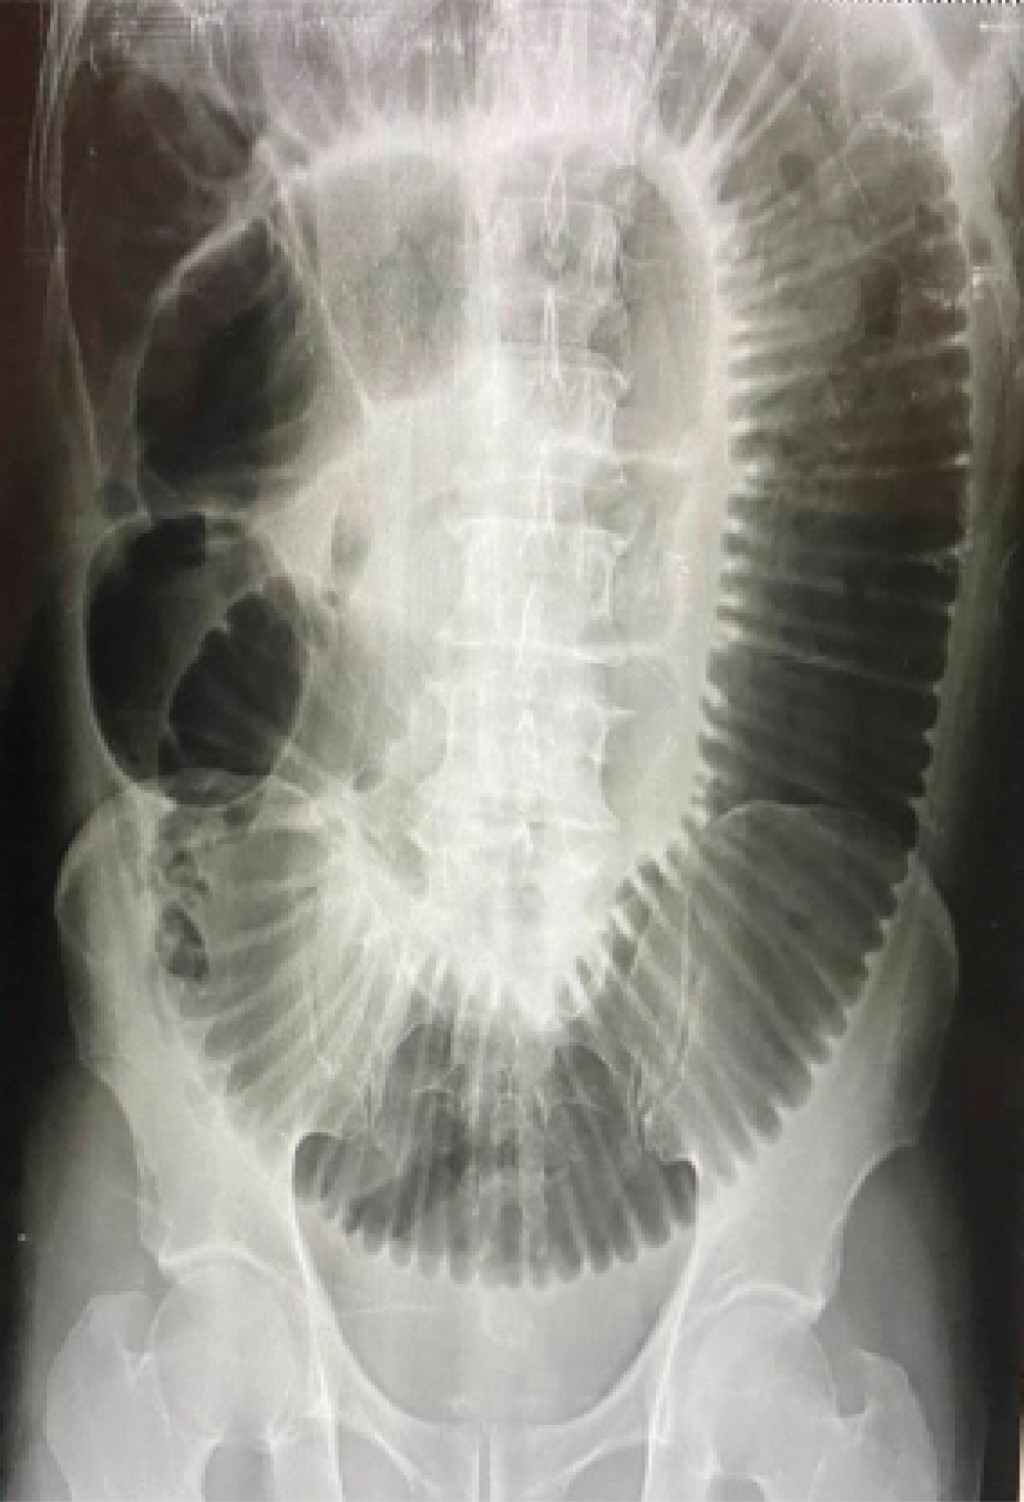

Laboratory findings are shown in Tables 2, 3 and 4. Plain abdominal radiography in the standing position showed the presence of slight bowel distention, inter loop edema with a coin stack image, and hydro-aerial levels without air in the colon (Figure 1). Simple abdominal radiography in the supine position showed a coin stacking and a duodenal bubble image (Figure 2).

Figure 2